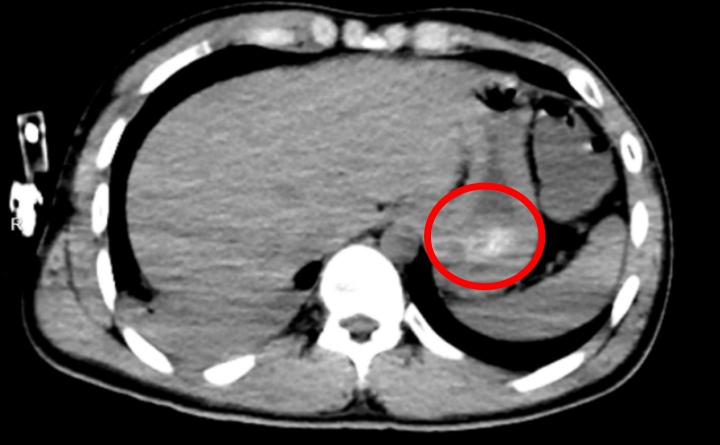

经全腹CT检查证实,林浩胃底存在大量团块状高密度影,也就是常规洗胃无法清除的“药石”,同时胸部CT显示其双肺出现渗出性病变,已引发吸入性肺炎。医生解释:

罪魁祸首就是胃里

持续释放毒性的”药石“